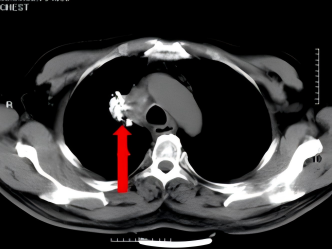

术后1年复查

术后9+年,患者再次到我院复查胸部CT,发现右上肺上方(尖段)新增结节,诊断为转移瘤,征得患者及家属同意后,再次为患者实施右上肺尖段新增结节碘125粒子植入技术,进一步为患者稳定病灶。

术后9+年复查

右上肺尖段新增结节碘125粒子植入